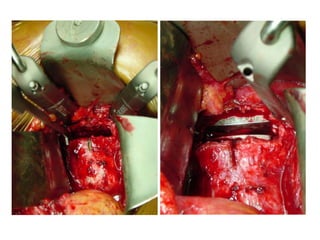

•Posterior procedure

•Trans S1 – L5 fibular graft

•Posterior stabilization (transpedicular screws and rods)